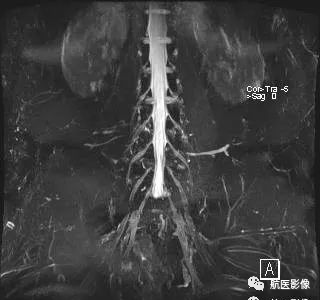

6. MR周围神经成像:

评估臂丛或腰骶丛的病变,如神经卡压综合征、血肿或肿瘤压迫神经、神经损伤等。

磁共振臂丛神经成像

MR腰骶丛成像